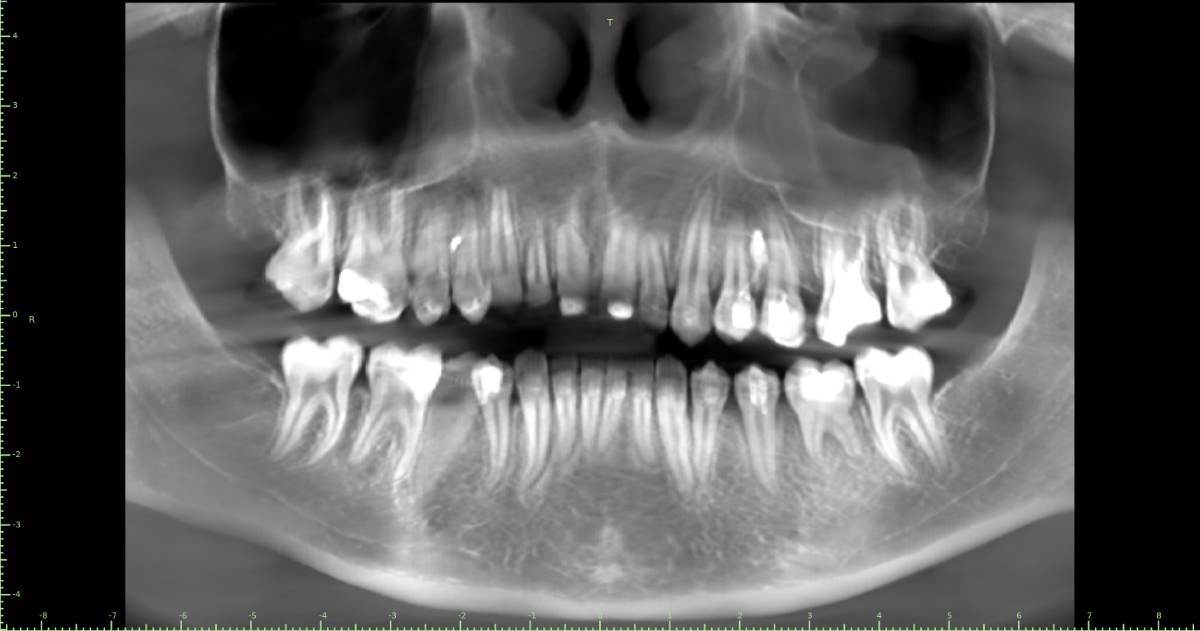

Женька Опубликовано 28 ноября, 2025 Поделиться Опубликовано 28 ноября, 2025 Всем привет, коллеги! 14 лет, терапевты ставят трещину по КТ (снимков до, к сожалению нет, косяк, каюсь). чуть сепарировав зуб и глянув на зуб под отлетевшим куском пломбы трещина "подтвердилась". Кейс на фото. Из интересного - маленький реколл в 1.5 года и спокойное перемещение зуба брекетами! 4 1 2 Ссылка на комментарий